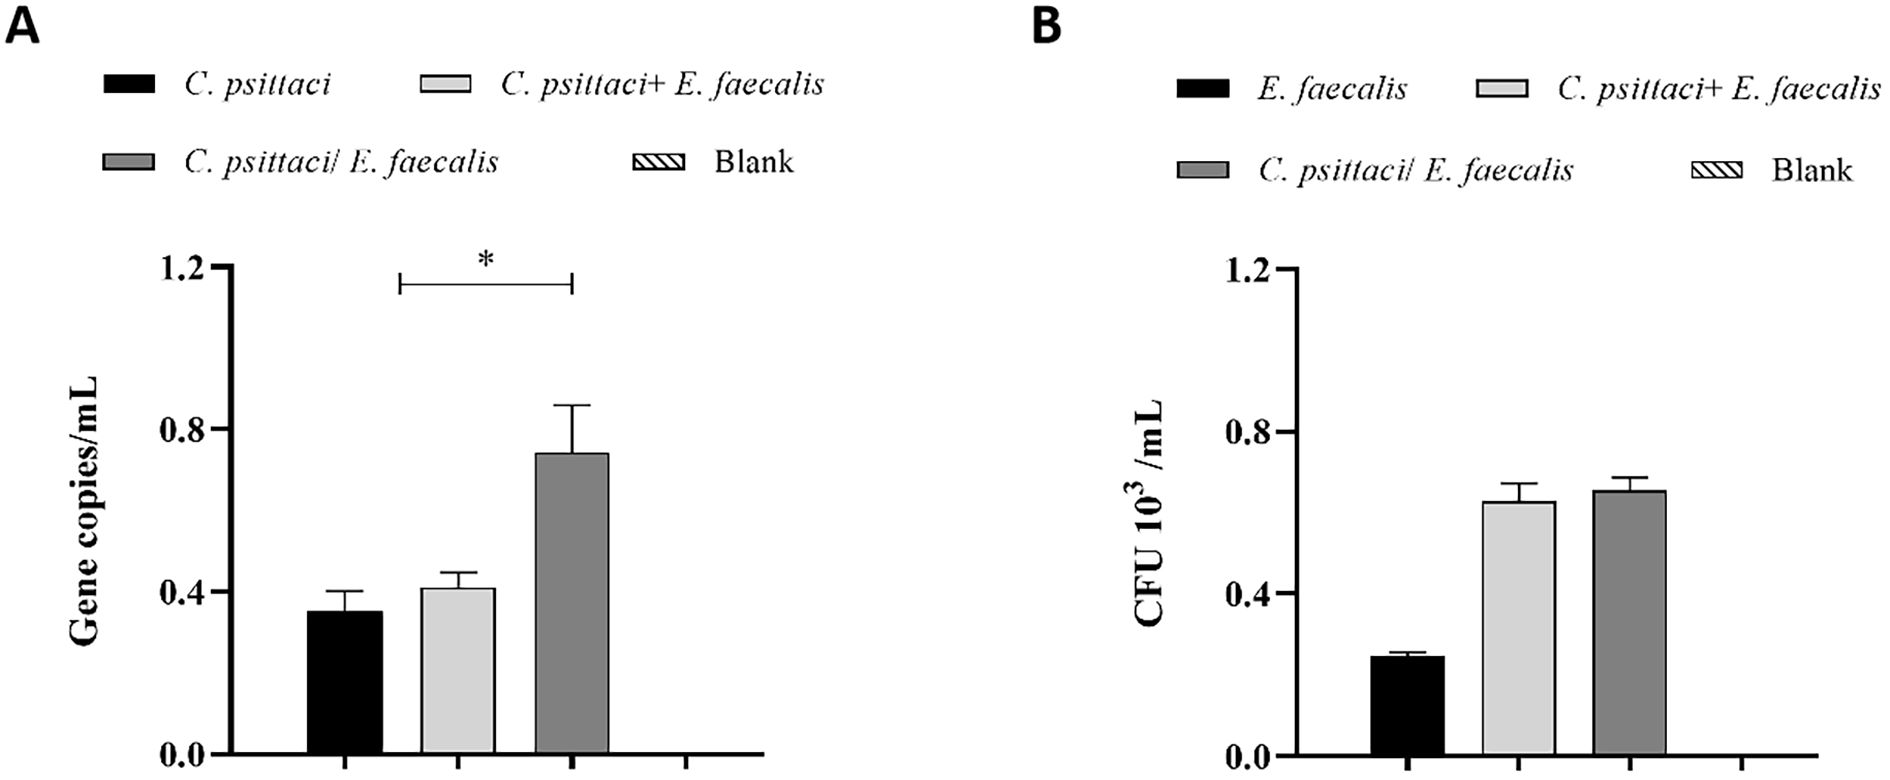

Regarding bacterial loads, high chlamydial loads were determined in the C. psittaci/E. faecalis group compared to the C. psittaci+E. faecalis group or C. psittaci alone group (p < 0.05) (Figure 9A). On the contrary, no significant difference in E. faecalis clearance was found between the C. psittaci/E. faecalis group and the C. psittaci+E. faecalis group (Figure 9b).

Figure 9. Determination of bacterial loads in the mouse lungs after coinfection with Chlamydia psittaci or Enterococcus faecalis. (A) C. psittaci loads in lungs on day 14 post-challenge. The symbol * indicates a statistically significant difference (p < 0.05). (B) E. faecalis loads in lungs on day 14 post-challenge. No significant difference in E. faecalis clearance was found between the C. psittaci/E. faecalis group and the C. psittaci+E. faecalis group (B). The differences were analyzed using ANOVA (p < 0.05, p < 0.01).